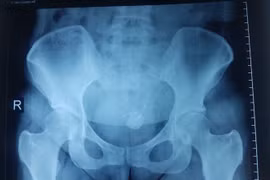

Bệnh nhân nữ 33 tuổi vào điều trị tại Bệnh viện đa khoa tỉnh Tuyên Quang sau khi xuất hiện triệu chứng tiểu buốt. Các bác sĩ sau đó xác định nguyên nhân gây bệnh là do vòng tránh thai “đi lạc“ vào ổ bụng.